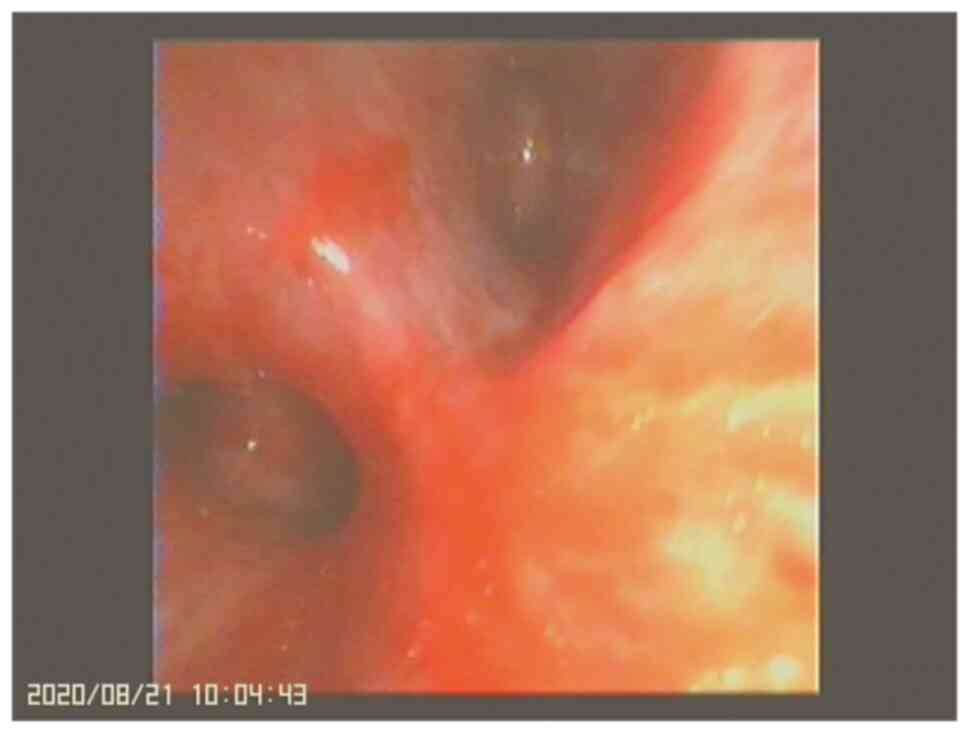

After the treatment with prednisone, propranolol, sirolimus and somatostatin, the clinical symptoms of the child were improved. At the same time, the patient underwent a thoracentesis and the drainage tube was removed after laboratory examination of the pleural effusion. In the treatment of pleural effusion, we chose conservative treatment instead of repeated drainage. Afterwards, the pleural fluid in B-mode chest ultrasound was not significantly increased, blood routine hemoglobin concentration was stable, and fibrinogen level was not progressively decreased. Thus, we can consider the treatment was effective. The child was discharged on June 4, 2020. After discharge, he did not have a fever or pale face. Regular blood routine examinations were performed, and hemoglobin level was maintained at 90-110 g/l. He did not have anhelation and could be supine. The child was admitted to the hospital for a second time on July 27, 2020, and planned to receive lymphangiography and occlusion. During hospitalization, the patient's condition worsened due to infection, and hemoptysis occurred. Bronchoscopy showed obvious congestion, erosion, and bleeding of the left bronchial mucosa (Fig. 5), which was considered as the cause of hemoptysis. During the second admission, the patient was treated with oral prednisone for anti-inflammation, propranolol for stabilizing endothelial cells, sirolimus for suppressing the immune response, piperacillin sodium and tazobactam sodium for anti-infection activity, along with somatostatin, and calcium and iron supplements, after which the patient's condition was stable. Lymphangiogram and occlusion were performed on August 20, 2020. The child's condition was continuously followed up and observed, and regular outpatient follow-ups were performed until April 2021. The child's condition is stable, and he has a normal diet, no cough, hemoptysis, anhelation, chest tightness, and other discomforts. Routine blood reexamination revealed a hemoglobin concentration of 110 g/l.

Figure 5

Bronchoscopy showed obvious congestion, erosion and bleeding of the left bronchial mucosa.